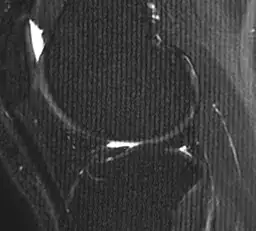

I am trying to find the frequency of the artifact on the MRI image of the knee below both manually and with ImageJ:

As you can see the artifact results in a bar pattern extending horizontally along the image - i.e. a spike artifact.